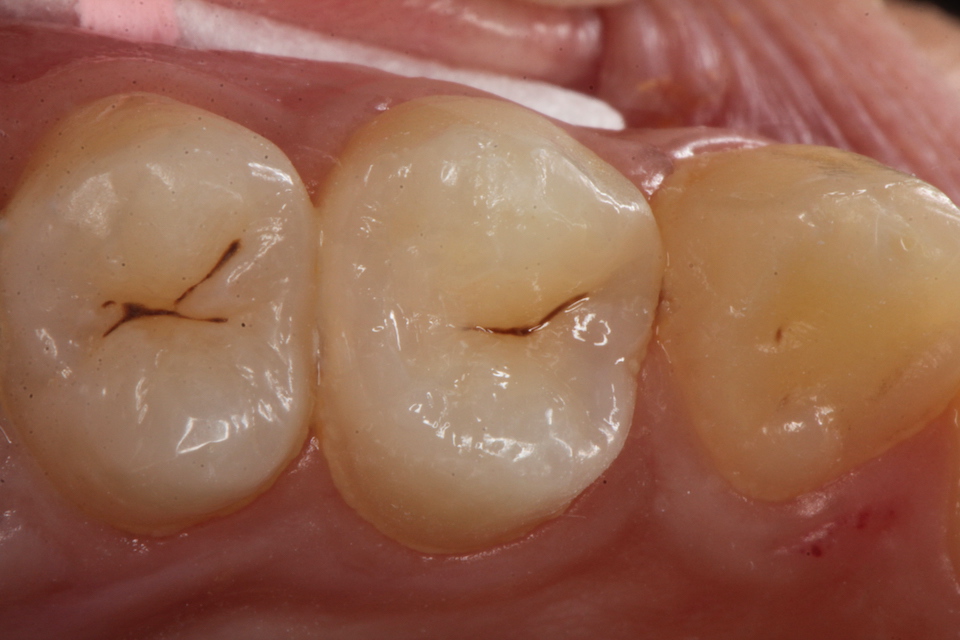

虫歯は金属の錆や腐食と同じ1.42 2025.11.10

虫歯は金属の錆や腐食と同じ1.41 2025.06.05